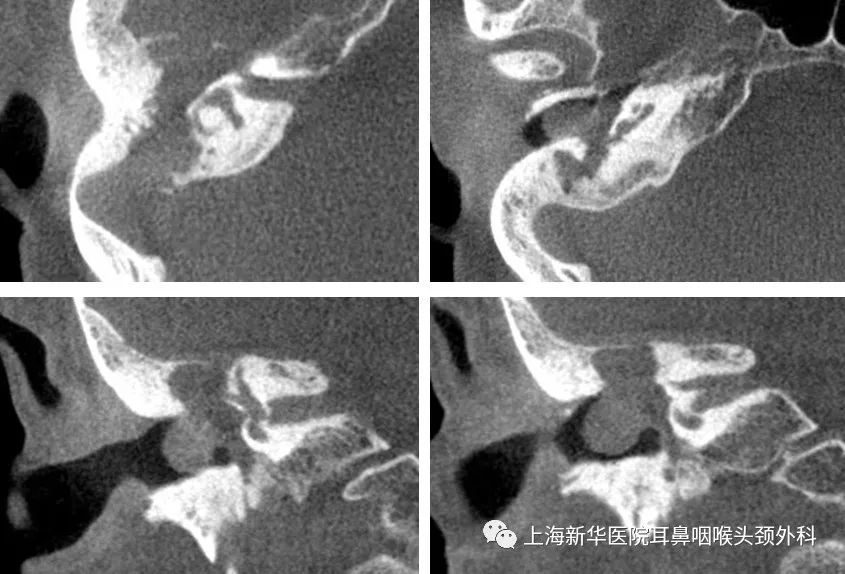

影像学检查:

术前CT